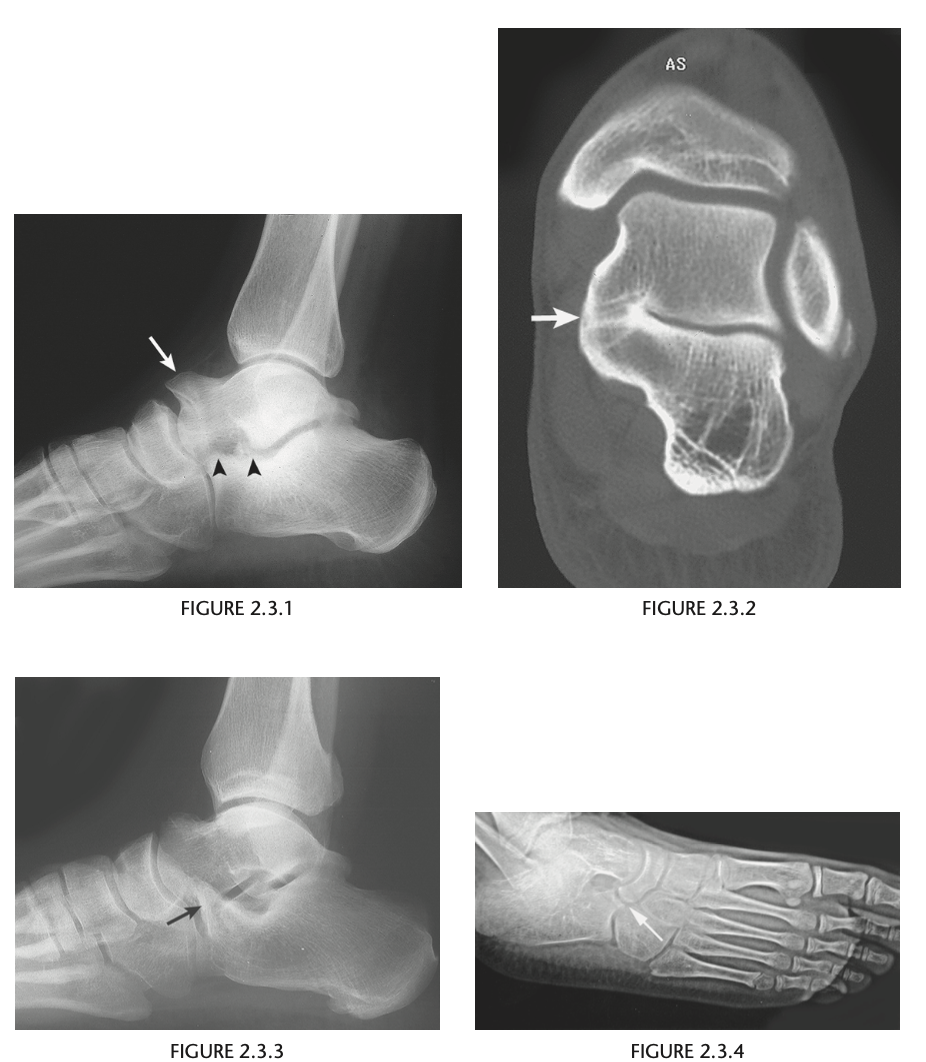

Foot pain

A lateral radiograph of the left foot demonstrates a prominent talar beak

­ (arrow) and bony sclerosis overlying the middle

facet (arrowheads). Coronal CT through the middle

facet shows talocalcaneal fusion, with bony bridging between the talus and the sustentaculum tali of the

calcaneus

Diagnosis: Tarsal coalition

abnormal fusion

of one or more of the tarsal bones, may be fibrous,

cartilaginous, or osseous and may be posttraumatic, or congenital.

Most

common tarsal coalitions are calcaneonavicular and

talocalcaneal.

Radiographically, calcaneonavicular coalition may

be suspected because of elongation of the anterior

facet of the calcaneus on radiographs (i.e., anteater

sign. CT can also be used to confirm coalition and shows

­ sclerosis at the articulation

Congenital coalition usually evolves from fibrous to osseous

coalition and may not be apparent on the initial

evaluation

Talocalcaneal coalition can result in dorsal beaking

of the talar head (Fig. 2.3.6, arrowhead), the so-called

C-sign (arrows)